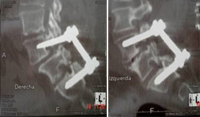

Izquierda: antes y después, espondilolistesis grado II tratada con implante percutáneo por el Dr. Morgenstern. Derecha: Implante percutáneo en canal estrecho